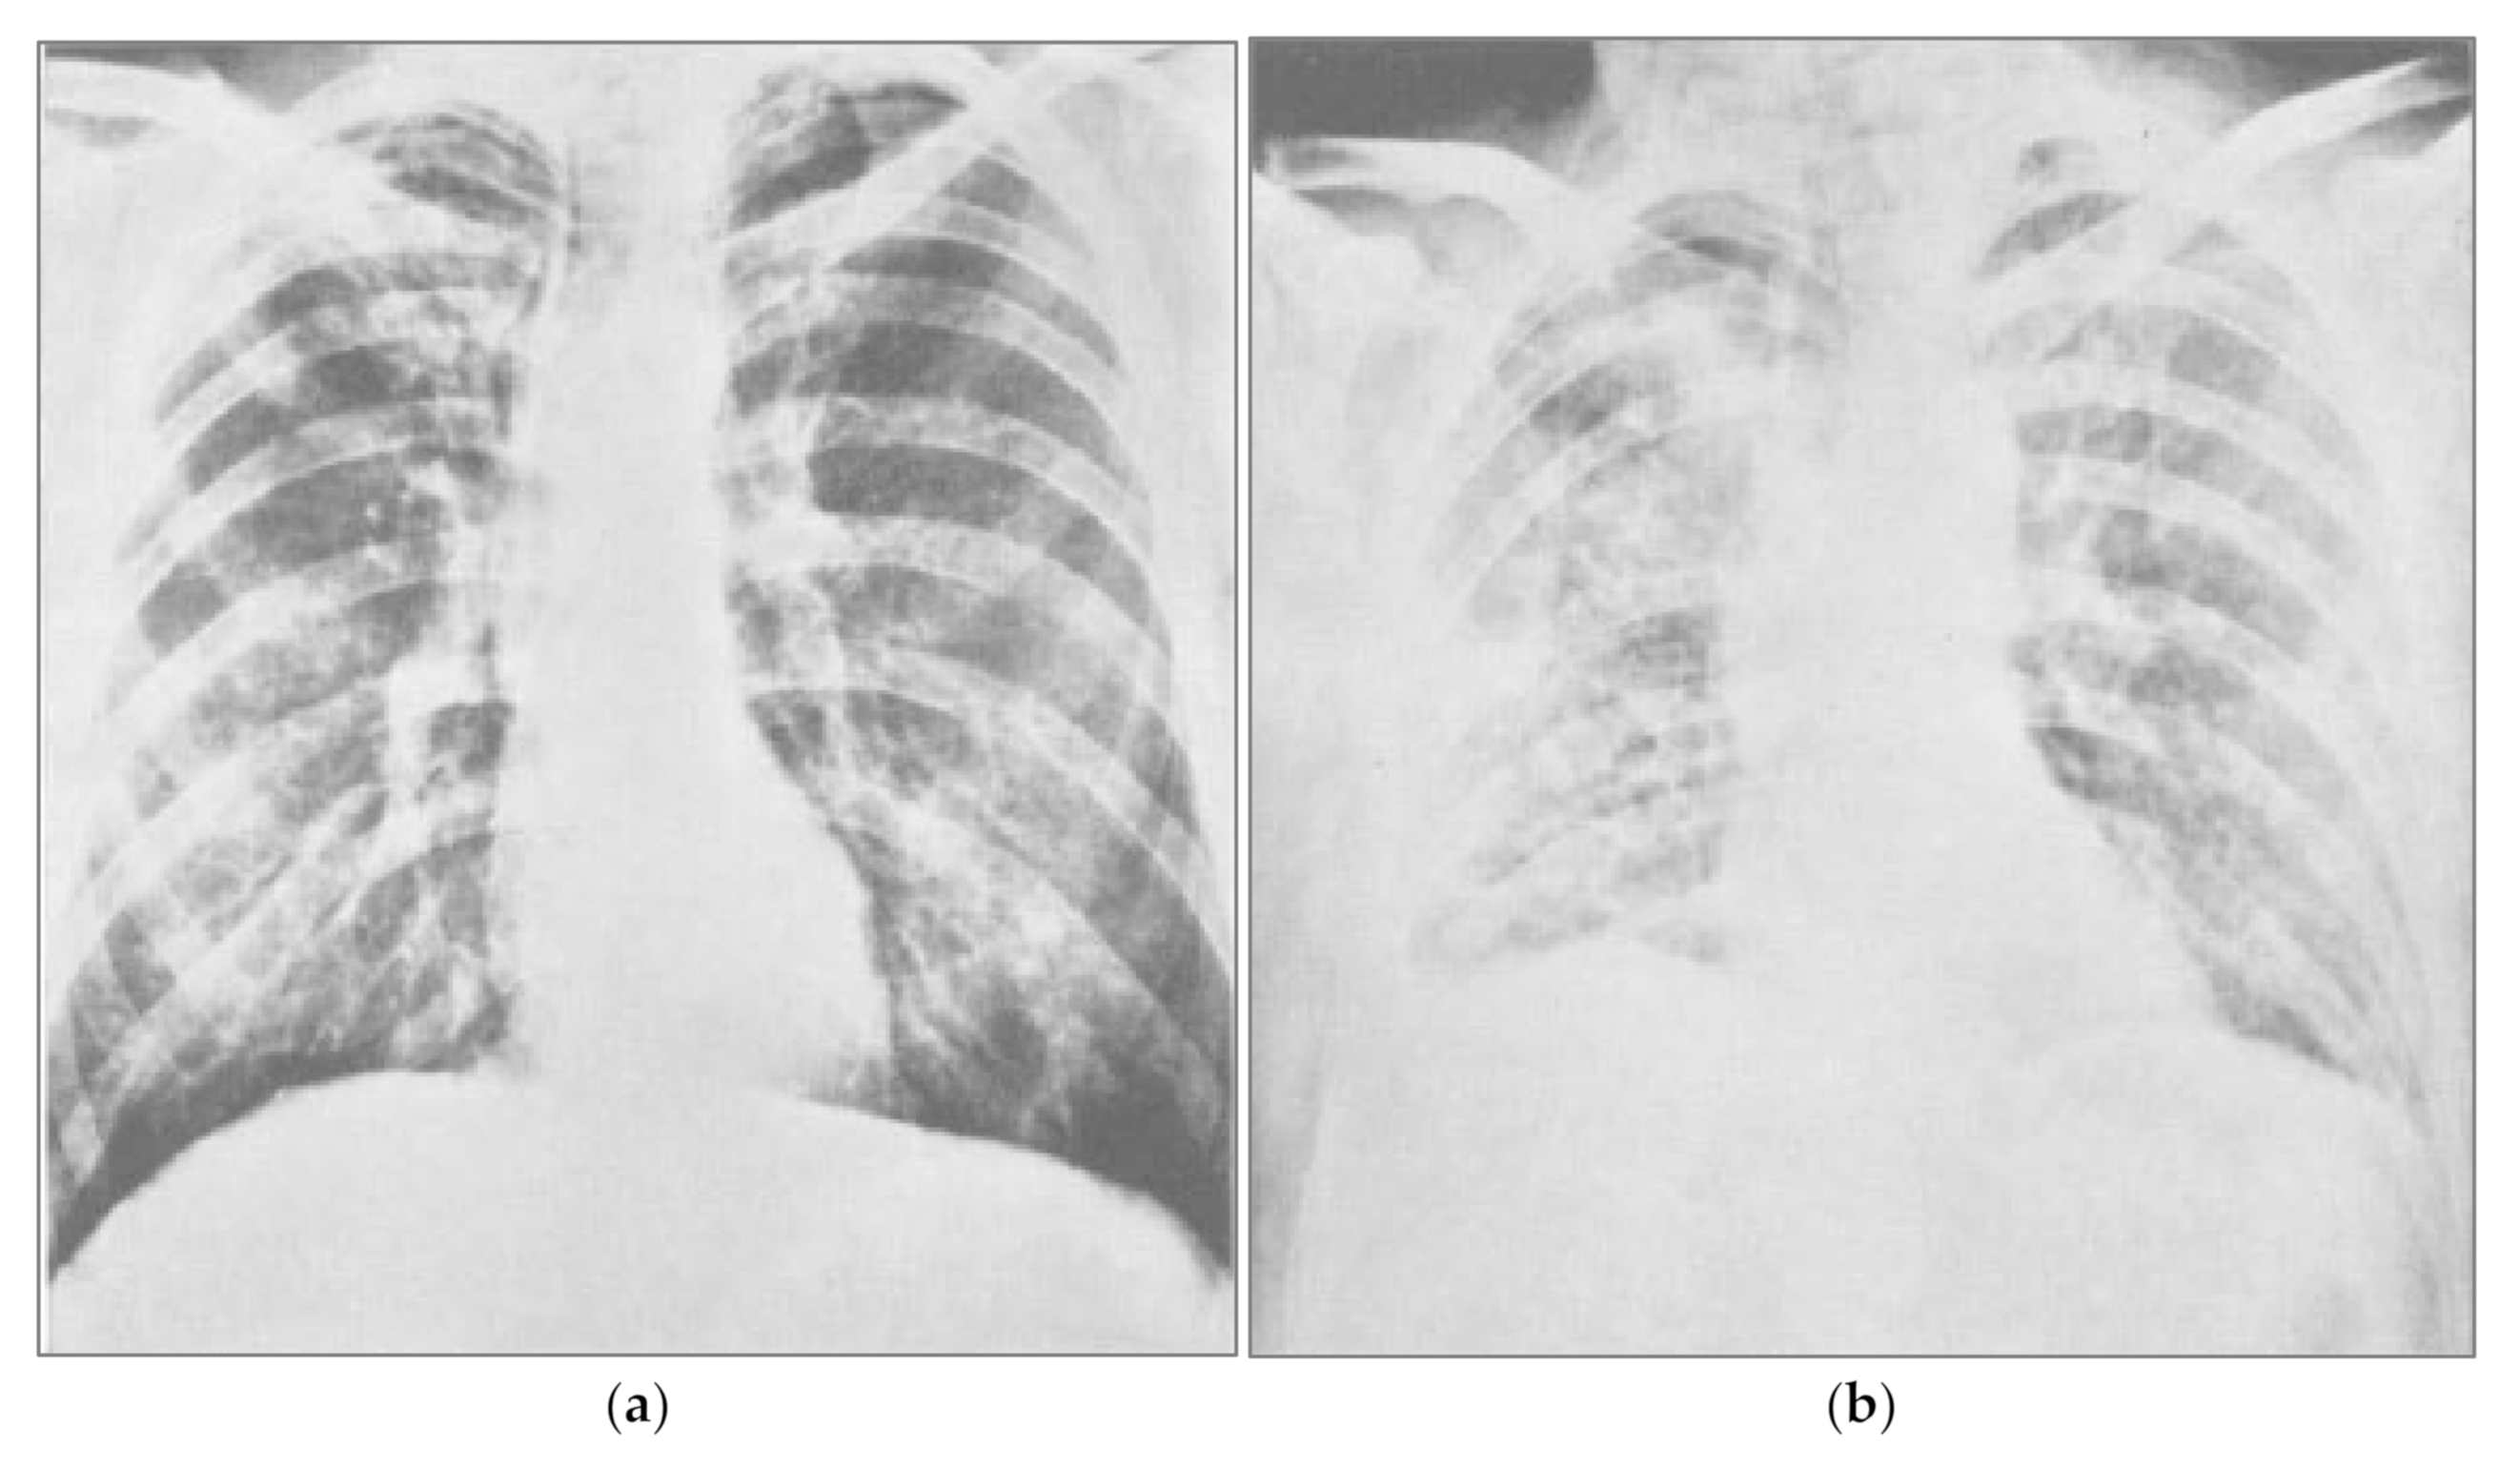

COVID-19 symptoms include fever, dry cough, fatigue, headache, and nasal congestion, and more serious symptoms include difficulty breathing [152]. Regardless of whether symptoms are due to acute cases or long-haul COVID-19 [153], sodium toxicity may play direct and indirect roles in many of these symptoms. In 1969, a controlled clinical trial tested the hypothesis that large infusions of sodium chloride and water would prevent fluid loss and hypovolemia related to complications in thoracic surgery [154]. After receiving sodium chloride infusions, some patients rapidly developed severe pulmonary congestion and fluid retention in the lungs, or pulmonary edema, which blocked respiration and lowered arterial oxygen pressure (pO2; Figure 1). One patient in the study died, and other patients who received infusions containing various concentrations of sodium chloride were placed on ventilators. These clinical experimental results demonstrate the harm of excessive sodium chloride and retained fluid in the lungs, causing pulmonary congestion, hypervolemia, and edema. The chest X-ray taken after sodium chloride infusion (b) is similar to the radiographs of drownings [155].

Figure 1.

Pulmonary congestion following sodium chloride infusion. (a) Patient before a large infusion of sodium chloride and water in a 1969 controlled clinical trial. (b) Same patient two days after infusion, showing severe congestion from pulmonary edema due to fluid retention. Reprinted from Hutchin et al., 1969 (132). Pulmonary congestion following infusion of large fluid loads in thoracic surgery patients, The Annals of Thoracic Surgery, 8(4), 339–347, with permission from Elsevier.